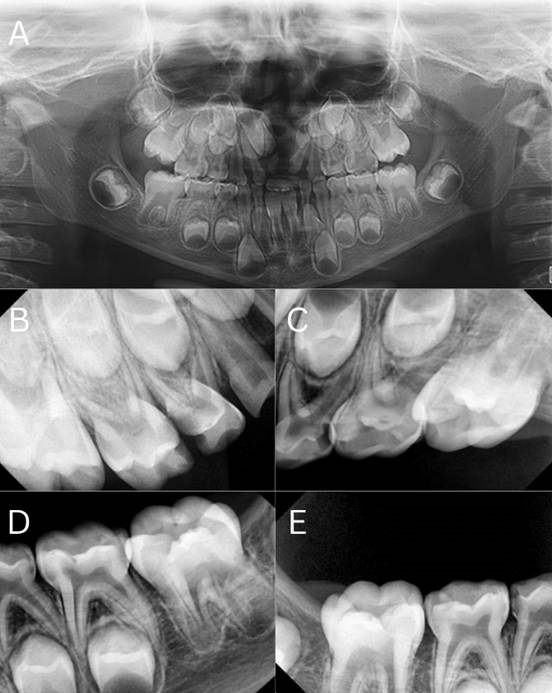

Radiographic Assessment

Radiographic assessment complemented the clinical findings. Panoramic radiography confirmed the congenital absence of the upper left central incisor (tooth 21). A series of periapical radiographs (PA) was obtained to evaluate the presence of radicular lesions, which revealed multiple primary molars requiring pulp therapy (Figure 2).

Figure 2. A) Panoramic Radiograph Showing the Congenital Absence of the Upper Left Central Incisor and the Cleft in the Alveolar Bone, B) Periapical Radiographs (PA) of the Upper Right Quarter, C) PA of the Upper Left Quarter, D) PA of the Lower Left Quarter, E) PA of the Lower Right Quarter